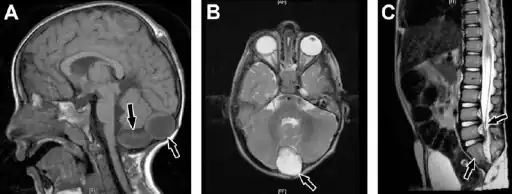

Caudal regression syndrome-a) Brain MRI shows 2 cystic structures at the region of cisterna magna b) cyst is also shown on axial T2-weighted image c) MRI dorsolumbar spine showing abrupt cutoff and bulbar configuration of conus medullaris at the level of L1 -